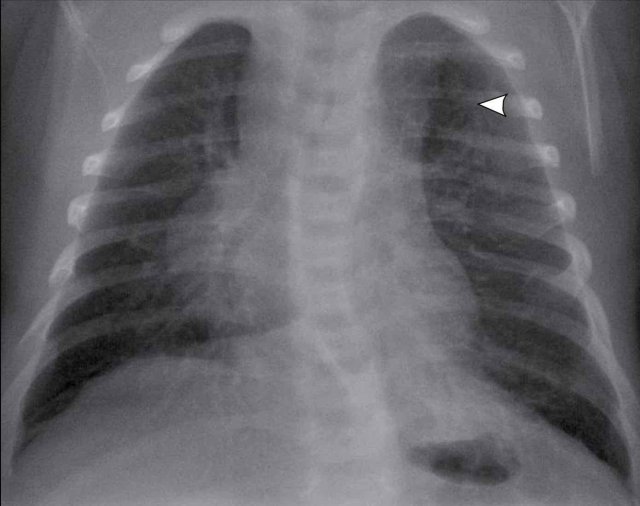

Images of a neonate with respiratory distress.

37 weeks gestational age

After primary caesarean section.

Left image

Hyperinflation on the left side.

Mild displacement of the midline structures to the right.

A pneumothorax is visible on the left side (arrow)

Right image

On the follow up chest x-ray, the pneumothorax has spontaneously resolved.